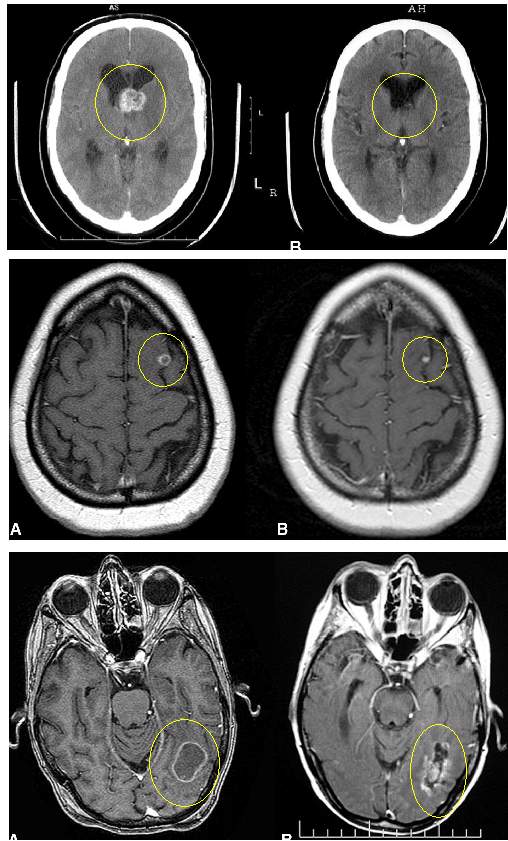

Serial imaging of 133 tumors showed that 99 tumors were smaller (74%), 22 tumors were

unchanged (17%), and 12 tumors were larger (9%). Four patients had a permanent neurologic

deficit after brain tumor management, and six patients underwent a resection after